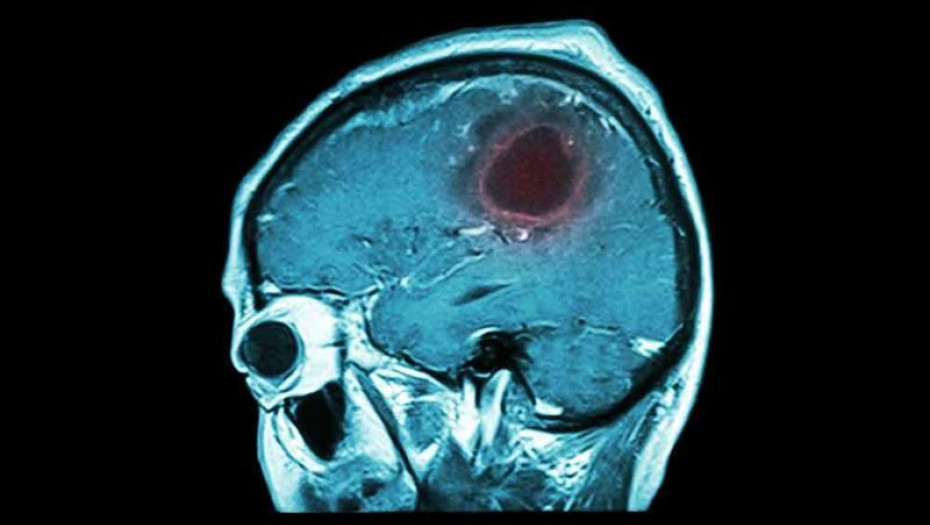

ΟΓΚΟΣ ΣΤΟΝ ΕΓΚΕΦΑΛΟ: ΤΑ 7 ΠΡΟΕΙΔΟΠΟΙΗΤΙΚΑ ΣΗΜΑΔΙΑ ΠΟΥ ΠΡΕΠΕΙ ΝΑ ΓΝΩΡΙΖΕΤΕ!

Οι όγκοι εγκεφάλου ποικίλλουν σε μέγεθος και σχήμα και τα συμπτώματά τους εξαρτώνται από το σημείο που αναπτύσσονται στον εγκέφαλο